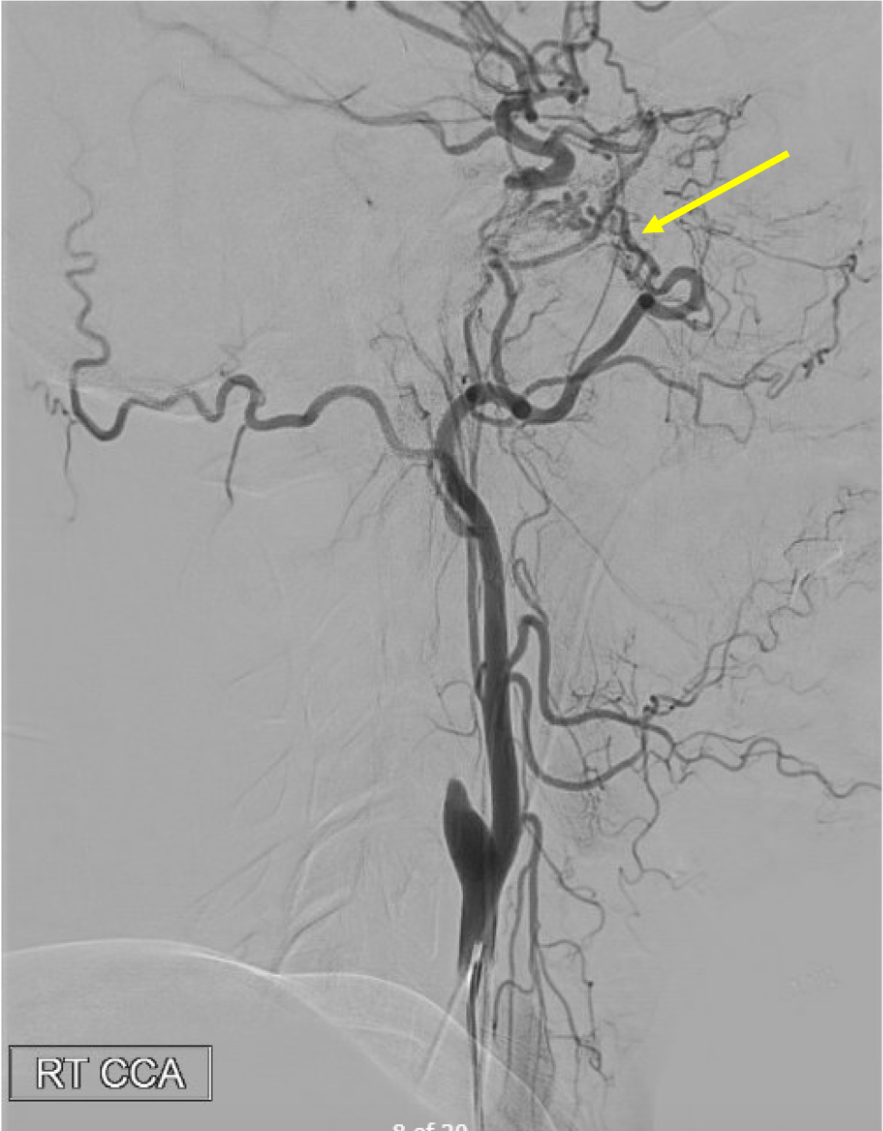

On this lateral view L ECA injection, name the vessel at the white arrow, which is the route of collateral between the ECA and ICA (yellow arrow) in this patient with longstanding ICA occlusion.

White arrow is the Ophthalmic artery-- here, likely collaterals from the ECA (through the internal maxillary artery --> ethmoidal artery) collateralize with the ICA through retrograde filling of the Ophthalmic